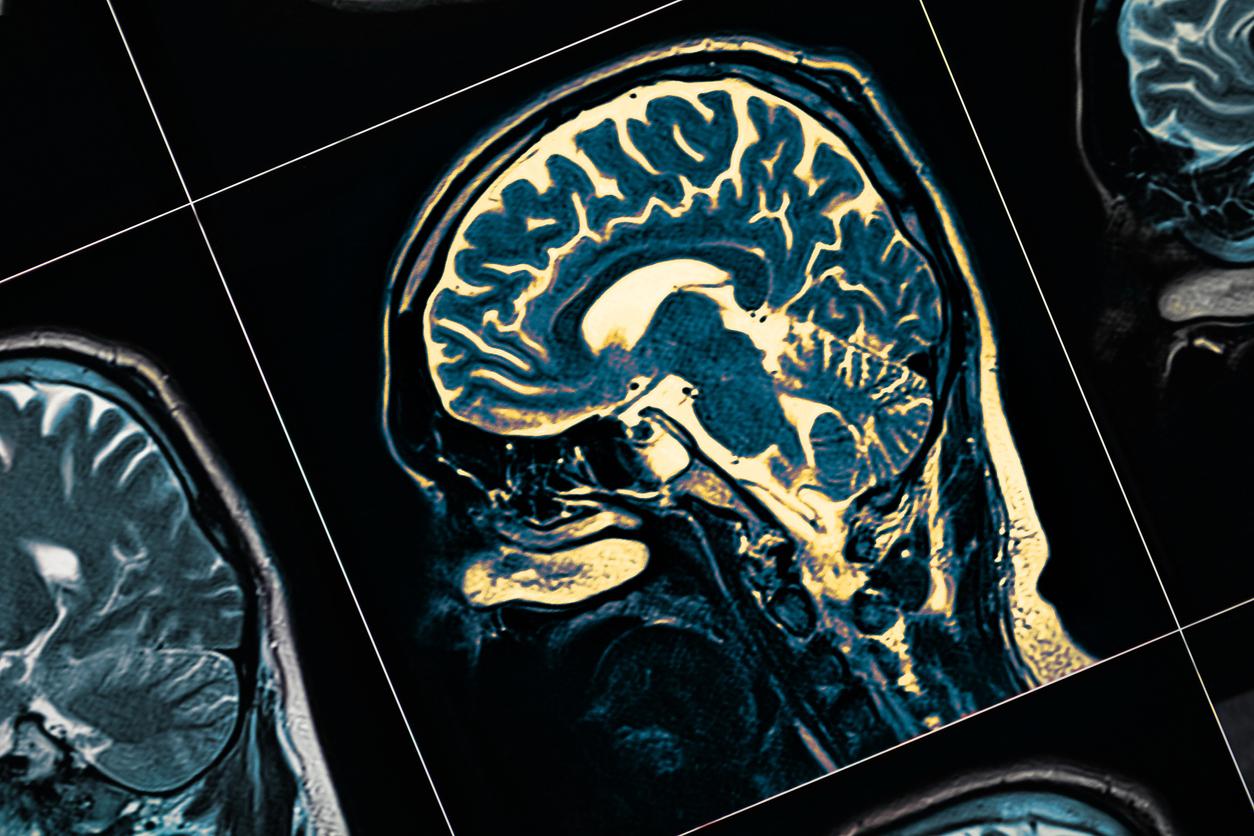

Ces nouveaux travaux montrent que même avant l’apparition de tout signe clinique, l’athérosclérose est associée à un faible métabolisme dans les régions du cerveau impliquées dans le développement de la démence. Les chercheurs ont utilisé l’imagerie avancée par tomographie par émission de positrons (TEP) afin de quantifier le métabolisme cérébral chez plus de 500 sujets. Ces derniers avaient un âge moyen de 50 ans et ne présentaient aucun symptôme, mais avaient déjà des signes d'athérosclérose dans leurs artères.

"Nous avons constaté qu'un risque cardiovasculaire plus élevé chez des personnes d'âge moyen apparemment en bonne santé était associé à un métabolisme cérébral plus faible dans les régions pariétotémorales impliquées dans la mémoire spatiale et sémantique et dans divers types d'apprentissage", détaille le Dr Cortés Canteli, co-auteur des travaux.

Plus spécifiquement, "les régions du cerveau présentant un faible métabolisme chez les participants à risque cardiovasculaire plus élevé sont les mêmes que celles touchées par la maladie d'Alzheimer", note le Dr Juan Domingo Gispert, chef du groupe de neuro-imagerie au BBRC. Cela suggère selon lui que "ces personnes pourraient avoir une vulnérabilité plus élevée que la normale à cette maladie".